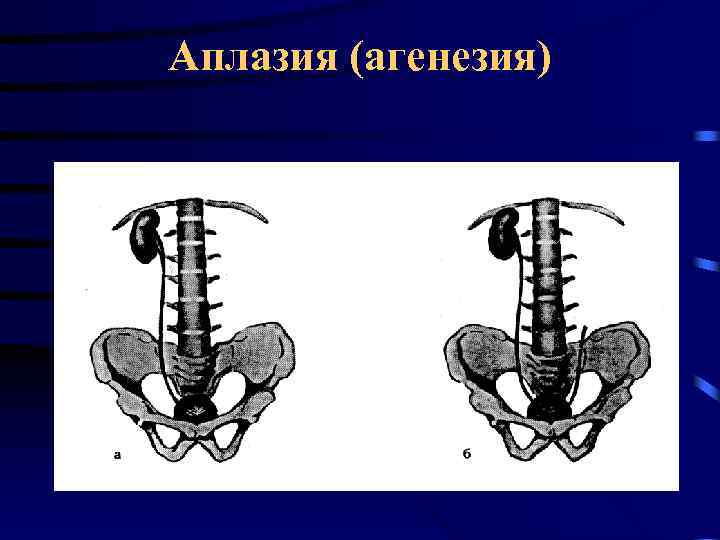

Аплазия (агенезия)

Аплазия (агенезия)

Аплазия (агенезия)

Аплазия (агенезия)